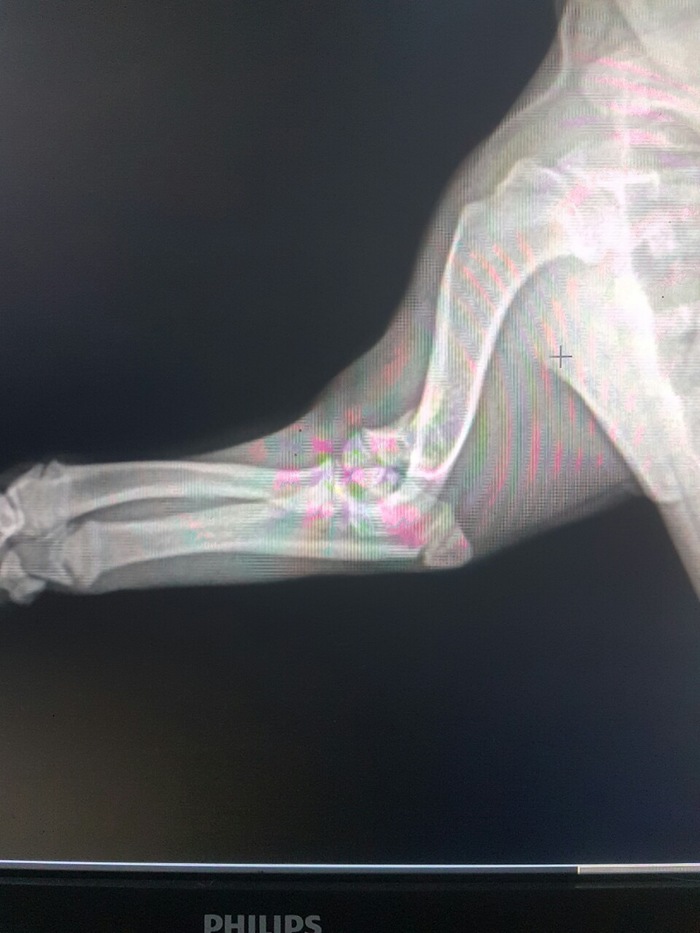

Нужна помощь ветеринара...

Просто слезно умоляю ветеринаров помочь.

Наша прекрасная Буля сломала лапку... это случилось пару часов назад и я до сих пор в шоке.. 😭

Ветеринар сказал, что нужна операция, но хочется быть уверенными, что это действительно необходимо.

Пожалуйста, если есть на просторах Пикабу ветеринары, скажите, на сколько все серьёзно?